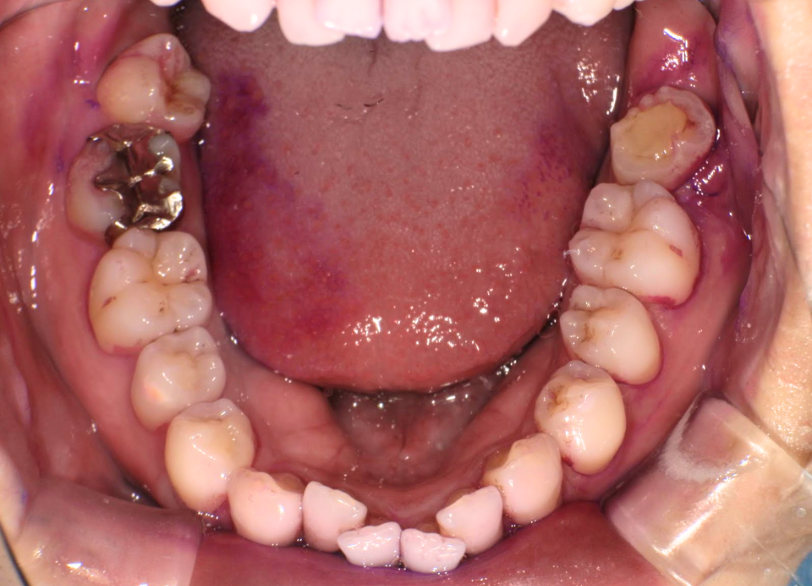

移植歯に対するエムドゲイン塗布および形状確認(抜歯時に破折してないかなど)

右上8を左下7へ移植完了

通院目的 抜歯と言われたが移植ができないか

診断 重度う蝕による抜歯